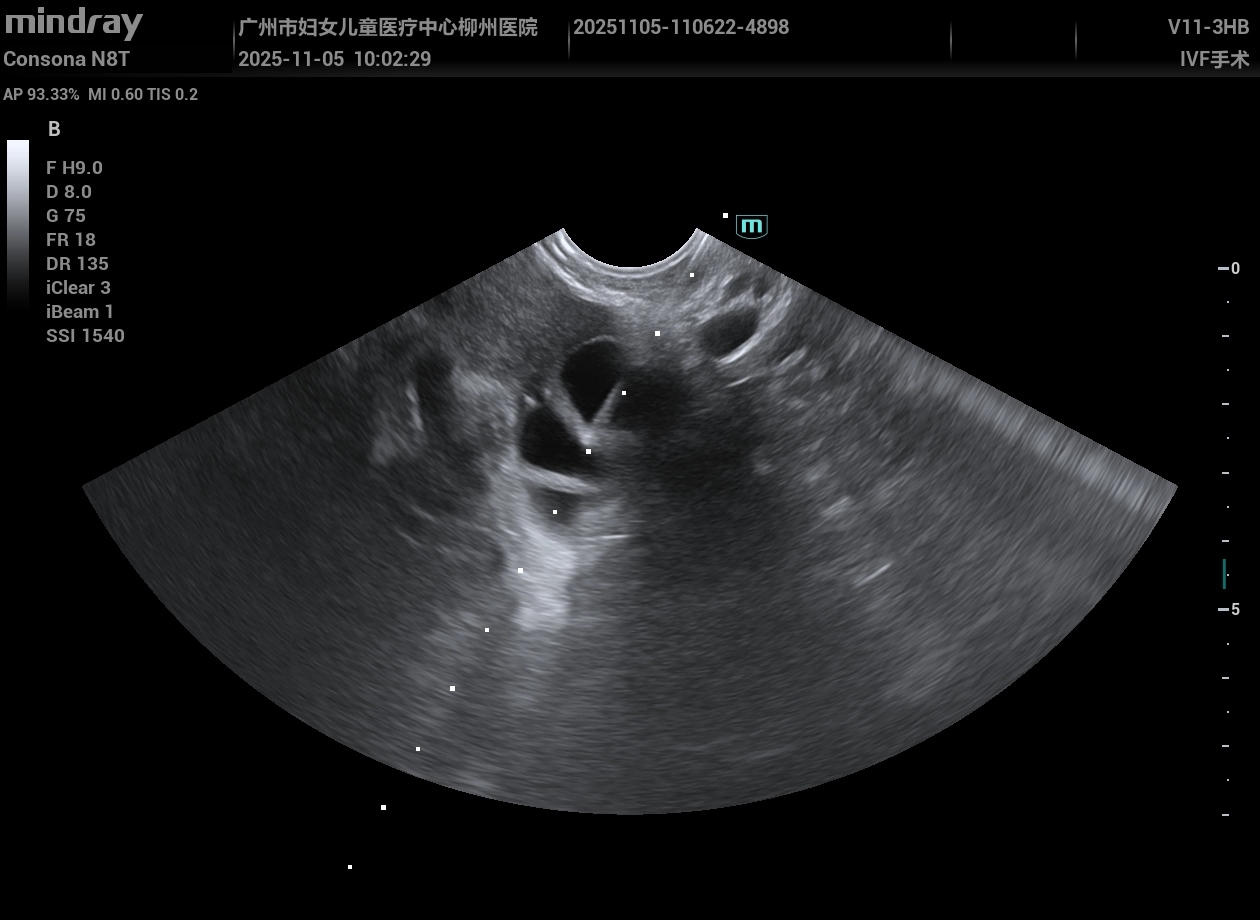

实例,超声可视化穿刺取卵细胞视频,弯把探头,操作方便快捷。